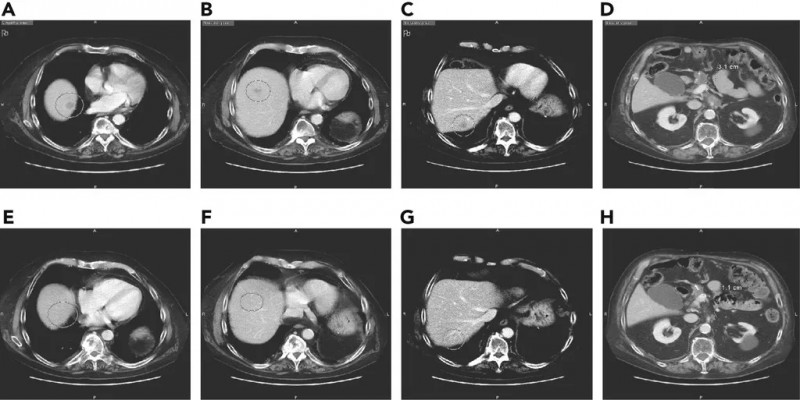

一位81岁高龄的老爷子,确诊时已是胰腺癌晚期。手术后不到半年就复发了,只能接受化疗,但胰腺癌侵袭性太强了,各种化疗方案根本阻挡不住病情的疯狂进展,癌症很快转移到了肝脏上,出现3个大小不一的病灶。

老爷子的身体每况愈下,家属也不抱太大希望了。命悬一线的时候,医生为他做了全基因组测序,在结果出来的那一刻,医生兴奋的告诉老爷子,他或许有救了!报告上写着存在SEL1L-NTRK1融合蛋白,这意味着老爷子能接受美国最新上市的“治愈系”抗癌药-拉罗替尼的治疗。对于存在NTRK融合的患者来说,拉罗替尼是一款能够改变生死的新药。而更幸运的是,老爷子成功入组了临床试验,可以免费接受治疗。

这一次,即便是面对最难治的“癌王”,拉罗替尼也显示出了强大的抗癌能力!我们直接说结果,在接受拉罗替尼治疗一年后,影像学检查显示,老爷子肝脏病变几乎完全消失(图2)。并且如此高龄的他对治疗完全耐受,既没有调整剂量也没有出现明显的不良反应。在文献发表时,患者接受了larotrectinib治疗已经13个月了。相信老爷子在现代精准医学的治疗下能长命百岁!